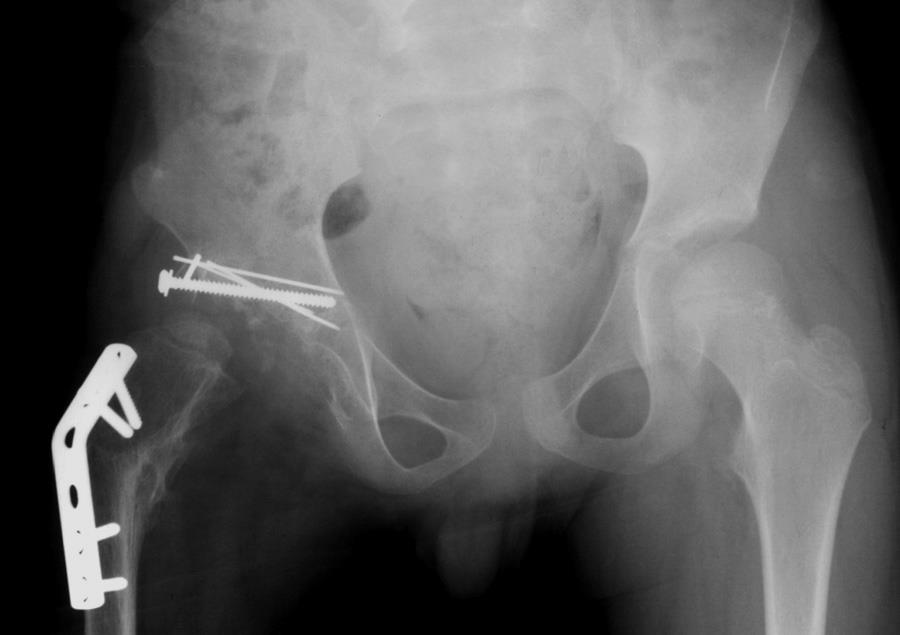

OSLO – Si chiama Alexander Selvik Wengshoel, è un artista norvegese ed è nato con una deformazione all’anca che lo costringeva alla sedia a rotelle. E quando ha ottenuto una protesi e si è operato (potendo così tornare a camminare) Alexander ha deciso, forse per vendetta, di mangiare parte della sua gamba amputata per inserire la protesi. Bollita e servita con patate e vino rosso.